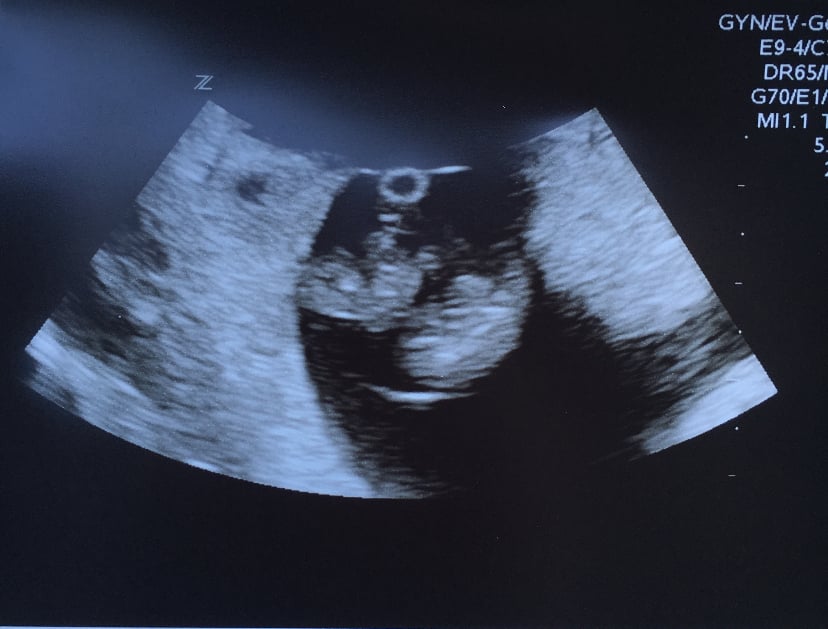

The pic I got from that visit again showed a big ball of baby but when you zoom in you can see a split down the baby which could indicate a separate sac or a membrane that separates identical's and it looks like two yolk sacks 🤷🏽‍♀️

I apologize that I haven’t had time to read through all of the responses but this was my 7 week scan with MoMo twins (same sac) if it gives you any sort of a reference.  Hope you get some answers/reassurance soon Mama.